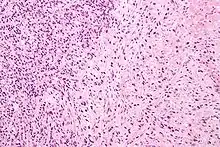

Gleason score 6 (3+3)

Gleason 3

Gleason 3 is a clearly infiltrative neoplasm, with extension into adjacent healthy prostate tissue. The glands alternate in size and shape, and are often long/angular. They are usually small/micro-glandular in comparison to Gleason 1 or 2 grades. However, some may be medium to large in size. The small glands of Gleason 3, in comparison to the small and poorly defined glands of pattern 4, are distinct glandular units. Mentally you could draw a circle around each of the glandular units in Gleason 3.[4][7]